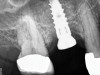

The implant is then delivered and should be well stabilized in the bone. If there is any mobility of the implant, it can either be placed a little deeper (if there is enough native bone) or the implant can be removed and the procedure aborted, in which case it would be a two-stage procedure. This should rarely occur with the tapered designed implant, even with only 2 mm of native bone. Using a bone-level platform-shifting implant (or a tissue-level designed implant) is critical, as the hard and soft tissue will establish a biologic width. If an external hex type of implant is used and the shoulder is placed at the bone level, an expected bone loss of 1.5 mm to 2 mm will occur.24 Figure 10 shows proper bone-level implant depth placement with a platform-shifting design. In this case, a 3-mm healing abutment was placed at the time of surgery to avoid a secondary uncovering surgery, but an implant-level healing abutment could have been placed instead. As can be seen, there was only about 2 mm to 3 mm of native bone height. The membrane was raised about 8 mm to 9 mm. Comparing the radiograph on the day of surgery (Figure 10) to the 6-month postoperative radiograph (Figure 11) shows no loss of native bone, as well as the positive change in appearance of the grafted bone. The 3.5-month CBCT scan (Figure 12) shows good healing of the bone with no coronal bone loss. With minimal native bone present, as in this case, the use of a non-platform-shifting or non-tissue-level implant design could be problematic. After 1.5 mm to 2 mm of crestal bone loss, an external hex designed implant could develop instability with possible implant failure. If a non-tapered implant is used and bone loss occurs during healing, migration of the implant into the sinus could potentially occur. The surgeon can use either a healing abutment or implant-level closure screw over the implant shoulder. With patients who tend to use their tongues to explore or play with the area, or if the area is under a removable partial denture, a closure screw is recommended.

A 74-year-old male patient presented with about 4 mm to 5 mm of native bone in the No. 4 position (Figure 17). A composite graft, as described in Case 1, was used, as was the same implant type, but the implant was 11.5 mm in length with a taper of 5 mm to 4.2 mm. The approximately 16-month post-healed floor of the sinus was raised about 7 mm to 8 mm (Figure 18). The CBCT scan taken at 16 months postoperatively showed no change in appearance from the area of the old floor of the sinus to the new bone formed (Figure 19). Although it was endodontically involved, tooth No. 15 was not extracted, against professional advice. As can be seen in Figure 18, the No. 14 implant is acting as a bridge abutment.

This patient was a 73-year-old man with only about 3.5 mm of native bone in the No. 3 site (Figure 20). The composite graft used here was a 50:50 mixture of DFDBA and deproteinized bovine bone mineral (Osteohealth, www.osteohealth.com) with approximately 40% calcium sulfate added. The implant was the same type and length as in Case 1 above. Figure 21 shows the area on the day of placement. In the CBCT scan on the day of placement (Figure 22), the native bone and bone graft were clearly discernable. However, the postoperative radiograph taken at 6.5 months (Figure 23) showed no marginal bone loss and a significantly denser appearance than when the graft was place. The membrane was raised about 7 mm to 8 mm. The final radiograph was taken after extraction of tooth No. 2 and after extraction of tooth No. 4 and immediate implant placement.